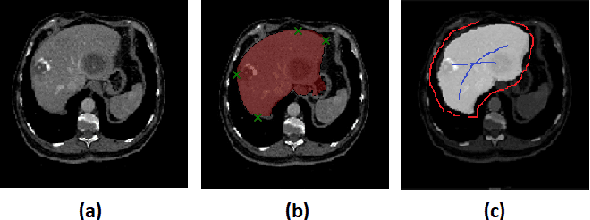

Abstract:Deep learning techniques have successfully been employed in numerous computer vision tasks including image segmentation. The techniques have also been applied to medical image segmentation, one of the most critical tasks in computer-aided diagnosis. Compared with natural images, the medical image is a gray-scale image with low-contrast (even with some invisible parts). Because some organs have similar intensity and texture with neighboring organs, there is usually a need to refine automatic segmentation results. In this paper, we propose an interactive deep refinement framework to improve the traditional semantic segmentation networks such as U-Net and fully convolutional network. In the proposed framework, we added a refinement network to traditional segmentation network to refine the segmentation results.Experimental results with public dataset revealed that the proposed method could achieve higher accuracy than other state-of-the-art methods.